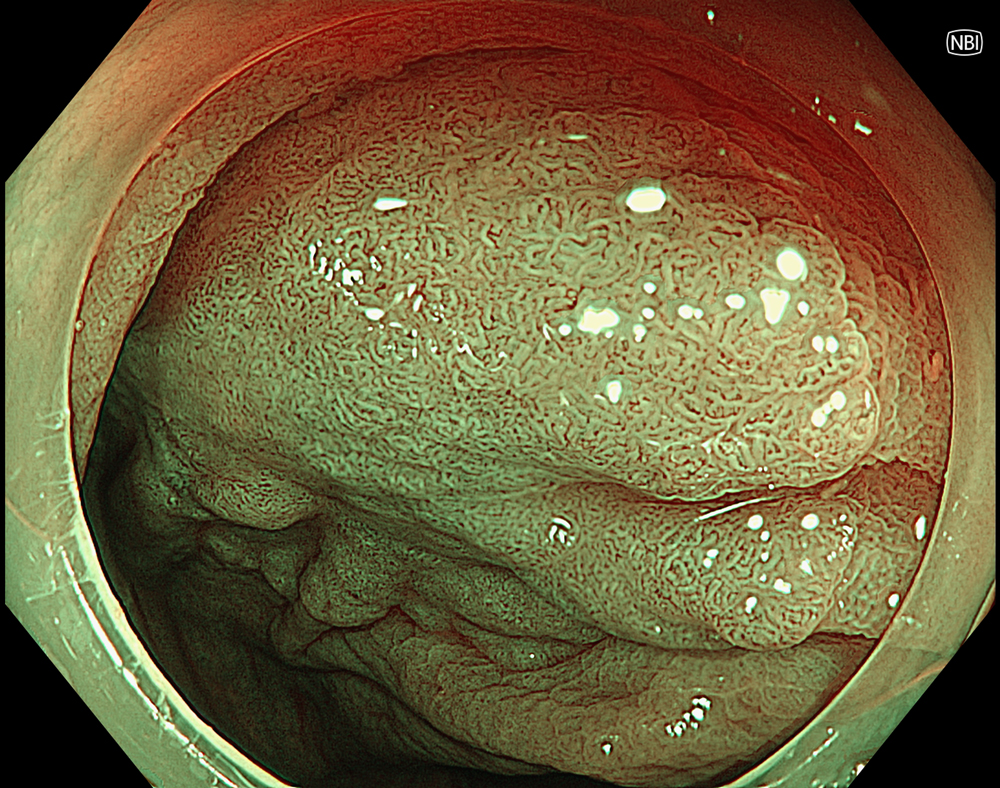

7. LST-NG in NBI

On NBI, the lesion shows suspected focal irregularity of the surface and vascular patterns, suggesting a JNET type IIb pattern.

8. NBI with magnification (Near focus)

Magnified NBI with near-focus observation more clearly demonstrates focal irregular surface and vascular patterns, consistent with a JNET type IIb pattern.